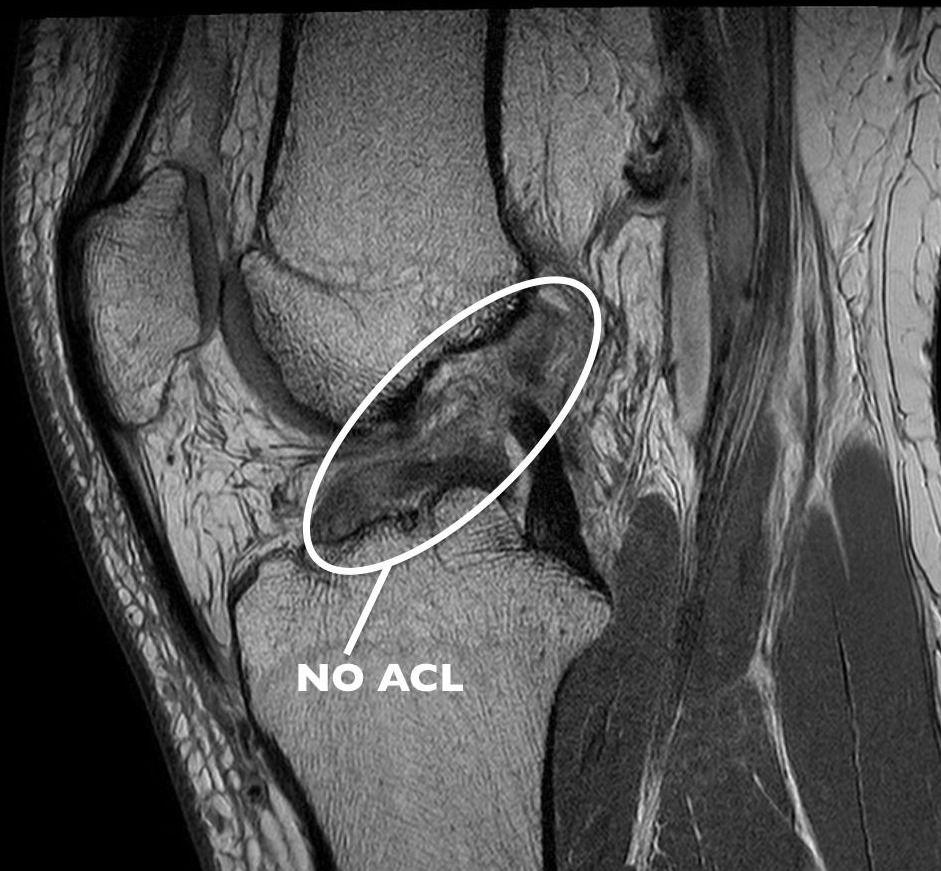

後續安排磁力共振影響檢查,確認是「右膝前十字韌帶撕裂」惹禍。所幸受傷部位僅部分撕裂,還不到全斷程度,毋須手術治療,建議採用注射PRP增生療法,雖然不能立刻下場劇烈跑跳,但大約2個多月後即恢復原有生活品質。

十字韌帶傷勢,可在磁力共振中清晰看到。